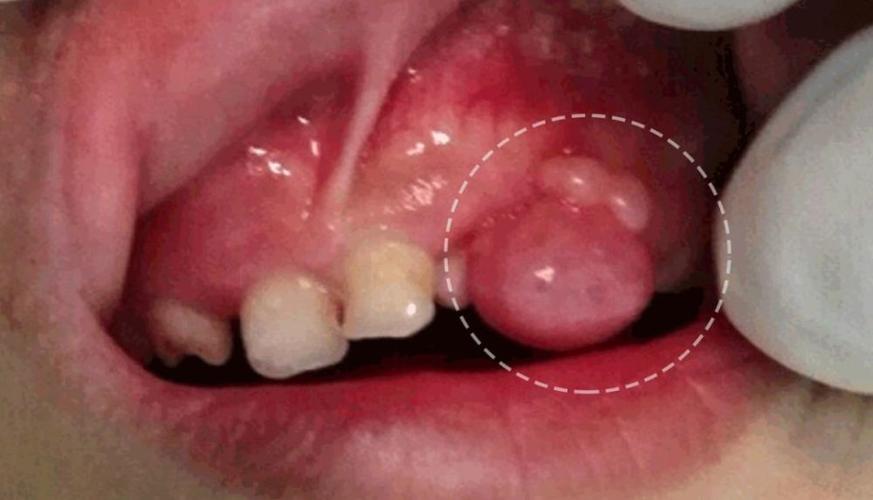

小朋友上牙龈长出了一个肉包,有懂的帮忙看

牙龈长包图片

小孩牙龈鼓包图片

小孩牙龈长个肉包图片

牙龈上长了个肉包图片